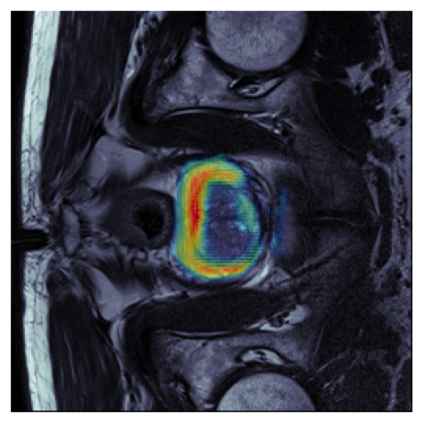

The sigmoid activation is the standard output activation function in binary classification and segmentation with neural networks. Still, there exist a variety of other potential output activation functions, which may lead to improved results in medical image segmentation. In this work, we consider how the asymptotic behavior of different output activation and loss functions affects the prediction probabilities and the corresponding segmentation errors. For cross entropy, we show that a faster rate of change of the activation function correlates with better predictions, while a slower rate of change can improve the calibration of probabilities. For dice loss, we found that the arctangent activation function is superior to the sigmoid function. Furthermore, we provide a test space for arbitrary output activation functions in the area of medical image segmentation. We tested seven activation functions in combination with three loss functions on four different medical image segmentation tasks to provide a classification of which function is best suited in this application scenario.